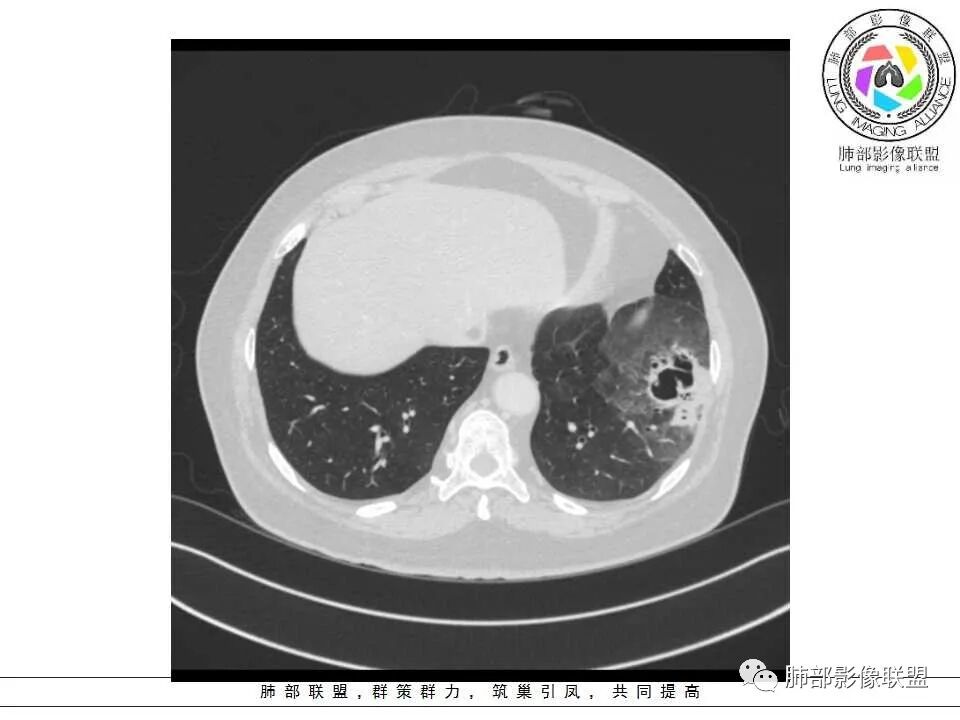

患者,女,65岁,2月余前受凉感冒后开始出现咳嗽,咳白痰,初发热2天,体温38℃左右,后降至正常,咳嗽无好转。近2日咳嗽加重,痰量增多,为黄白痰,无发热,无乏力、盗汗,无胸痛、胸闷,无头晕、头痛,无恶心、呕吐。PET-CT检查提示炎性病灶与恶性结节鉴别困难。

病灶分两部分

周围大片GGO

中央囊实性病变

南边:

病史没提咳血,周围出血灶似乎不太好说

部分边界偏清

囊腔有张力,外形有分叶,壁厚薄不均,有间隔,有强化

哪些病变可能?

1、癌

2、炎性:曲霉菌?

3、良性:囊腺瘤样畸形合并感染

1、左肺下叶外基底段不规则囊腔样病灶,囊腔内有条形影及血管穿行。

2、囊壁薄厚不均匀,稍显僵硬,有壁结节(对应边缘分叶等)、结节强化明显。

以上两条几乎将肺囊肿彻底排除在外,且高度怀疑新生物!

3、灶周环以大范围磨玻璃影,非常均匀,没有重力分布趋势,分叶状,边界隐约可变。

4、冠状位部分层面可见支气管在囊腔边缘截断。

本例囊腔性病灶尽管腔壁稍显僵硬,壁结节凸显,但女性患者,灶周明显磨玻璃晕,都强烈提示为囊腔性腺癌。

病理粘液腺癌确乎意外,非常罕见!

大范围磨玻璃影可以符合粘液腺癌。机制包括分泌黏液的癌细胞沿肺泡壁生长以及含肿瘤细胞的黏液成分沿气道飘散种植等。囊腔形成推测肿瘤等成分形成小支气管的活瓣阻塞所致。

周围磨玻璃影不支持炎性渗出,没有沿气道分布,边缘较清楚;未形成肺泡结节,出血也不符合,且患者临床无咯血。